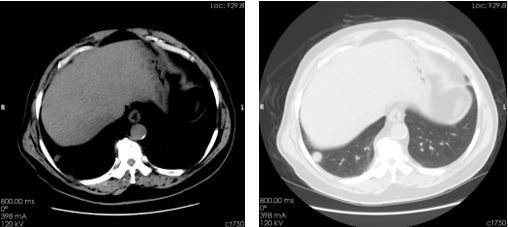

右肺下叶基底段示一孤立结节,边缘清晰

右肺结节能谱曲线与右肾上极肿块完全重合(图示为黄色和红色曲线) 临床分析与诊断: 该患者右肾肿瘤是典型的透明细胞癌表现,右肺孤立结节通过能谱曲线分析,两者完全重合,诊断为右肾透明细胞癌并右肺下叶转移瘤。 右肾肿瘤后经术后病理证实为肾透明细胞癌,右肺结节亦经随访证实,说明CT的临床诊断准确清楚。 病例小结: 能谱四大工具之一的能谱曲线,可以通过比较两者曲线的斜率及走行对疑似转移病灶进行更进一步的分析,以明确是否同一来源抑或是不同性质的病变,可为临床提供更准确的判断和更多有价值的信息,从而达到诊断及鉴别诊断的目的。 临床小知识: 肾透明细胞癌来源于肾小管上皮细胞的腺癌,癌中常有出血、坏死、囊变和钙化。生于肾实质内,长大后浸润、压迫、破坏肾盂肾盏,向肾包膜外发展,形成血管瘤栓或转移到淋巴结及其他脏器。肾透明细胞癌早期常无症状,或症状较隐匿。可能有轻微的发热、乏力等全身症状,肿瘤体积增大时才被发现。临床主要表现为血尿、肾区疼痛和肿块等。 病例来源:聊城市第三人民医院